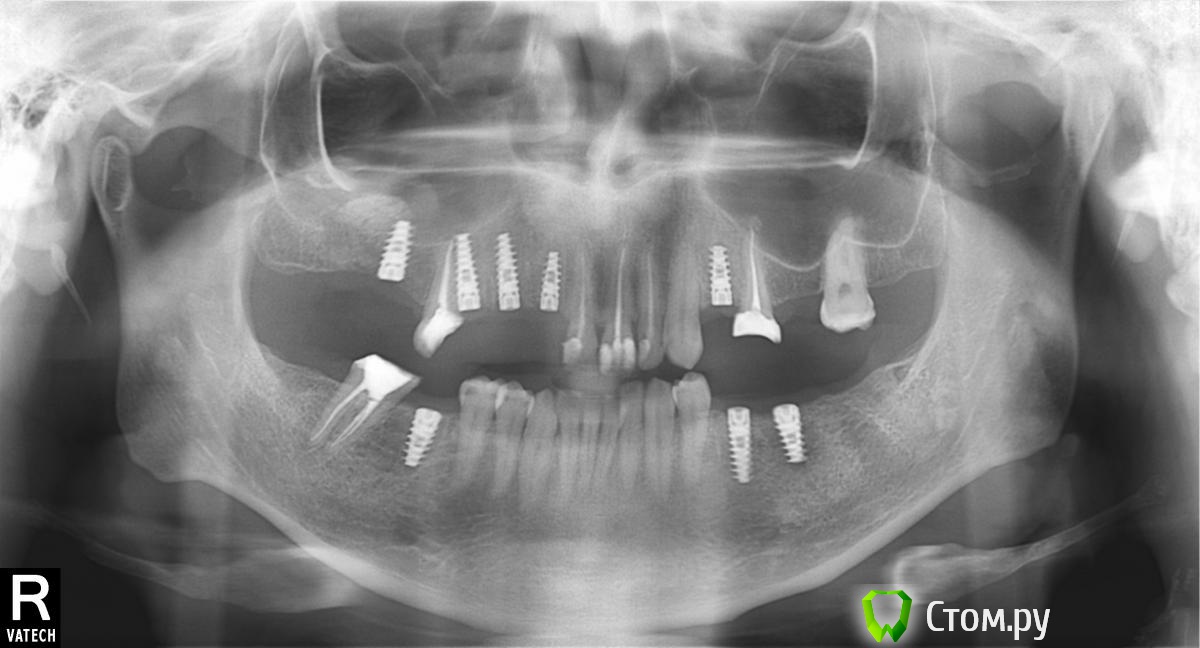

66666 Опубликовано 21 сентября, 2014 Поделиться Опубликовано 21 сентября, 2014 мне кажется, что имплант задел рядом стоящий корень зуба. после процедуры пропала чувствительность пятого зуба справа сверху. этот зуб предлагают зачем то удалить... сделал снимок, покажу его только в пятницу... много косяков натворили? Ссылка на комментарий

kriokov Опубликовано 21 сентября, 2014 Поделиться Опубликовано 21 сентября, 2014 не увидел никаких дефектов. Пятый удалил бы, на конструкцию .это никак не повлияет, а целесообразность использования его под восстановление коронкой сомнительно. ИМХО 2 Ссылка на комментарий